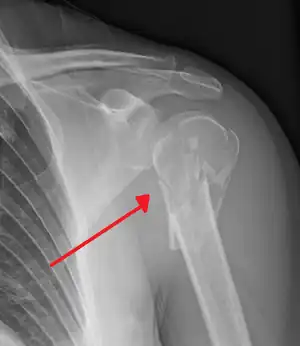

Surgical neck

The surgical neck is a narrow area distal to the tubercles that is a common site of fracture. It makes contact with the axillary nerve and the posterior humeral circumflex artery.

The axillary nerve is located at the proximal end, against the shoulder girdle. Dislocation of the humerus's glenohumeral joint has the potential to injure the axillary nerve or the axillary artery. Signs and symptoms of this dislocation include a loss of the normal shoulder contour and a palpable depression under the acromion.

Fracture of the proximal humerus